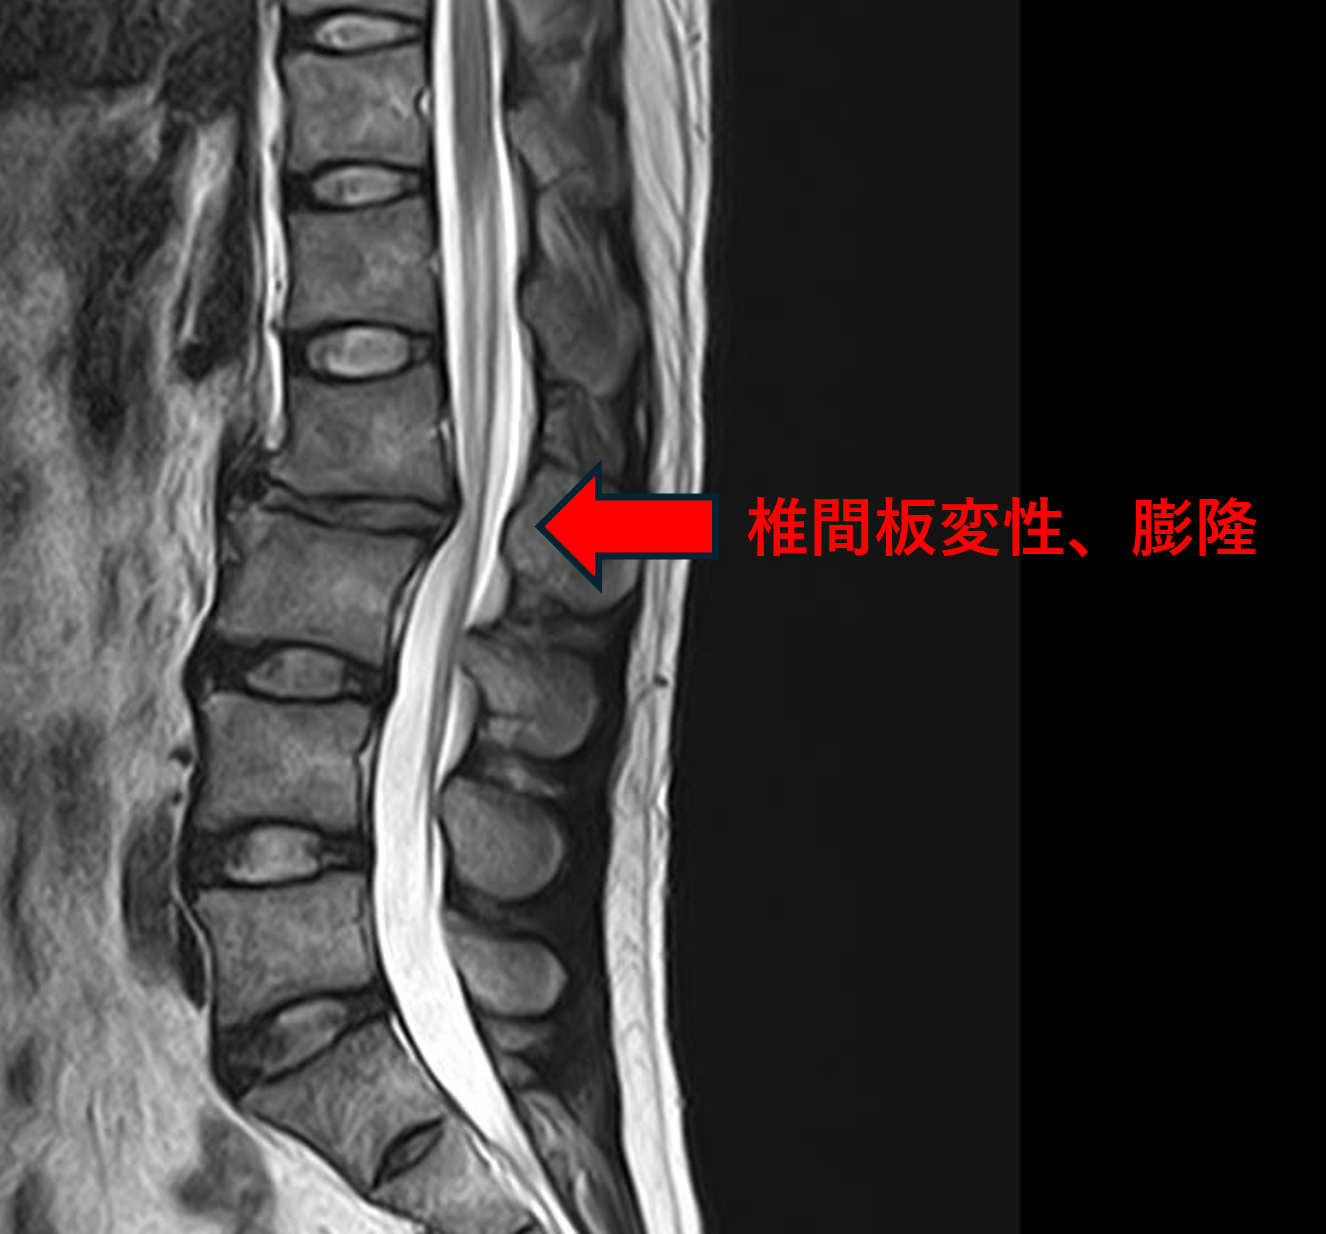

画像及び所見について

- L2/3 – 椎間板変性、膨隆

以上のことが画像上認められました。

L2/3の椎間板所見による脊柱管の圧排が、症状の原因の可能性が高い。